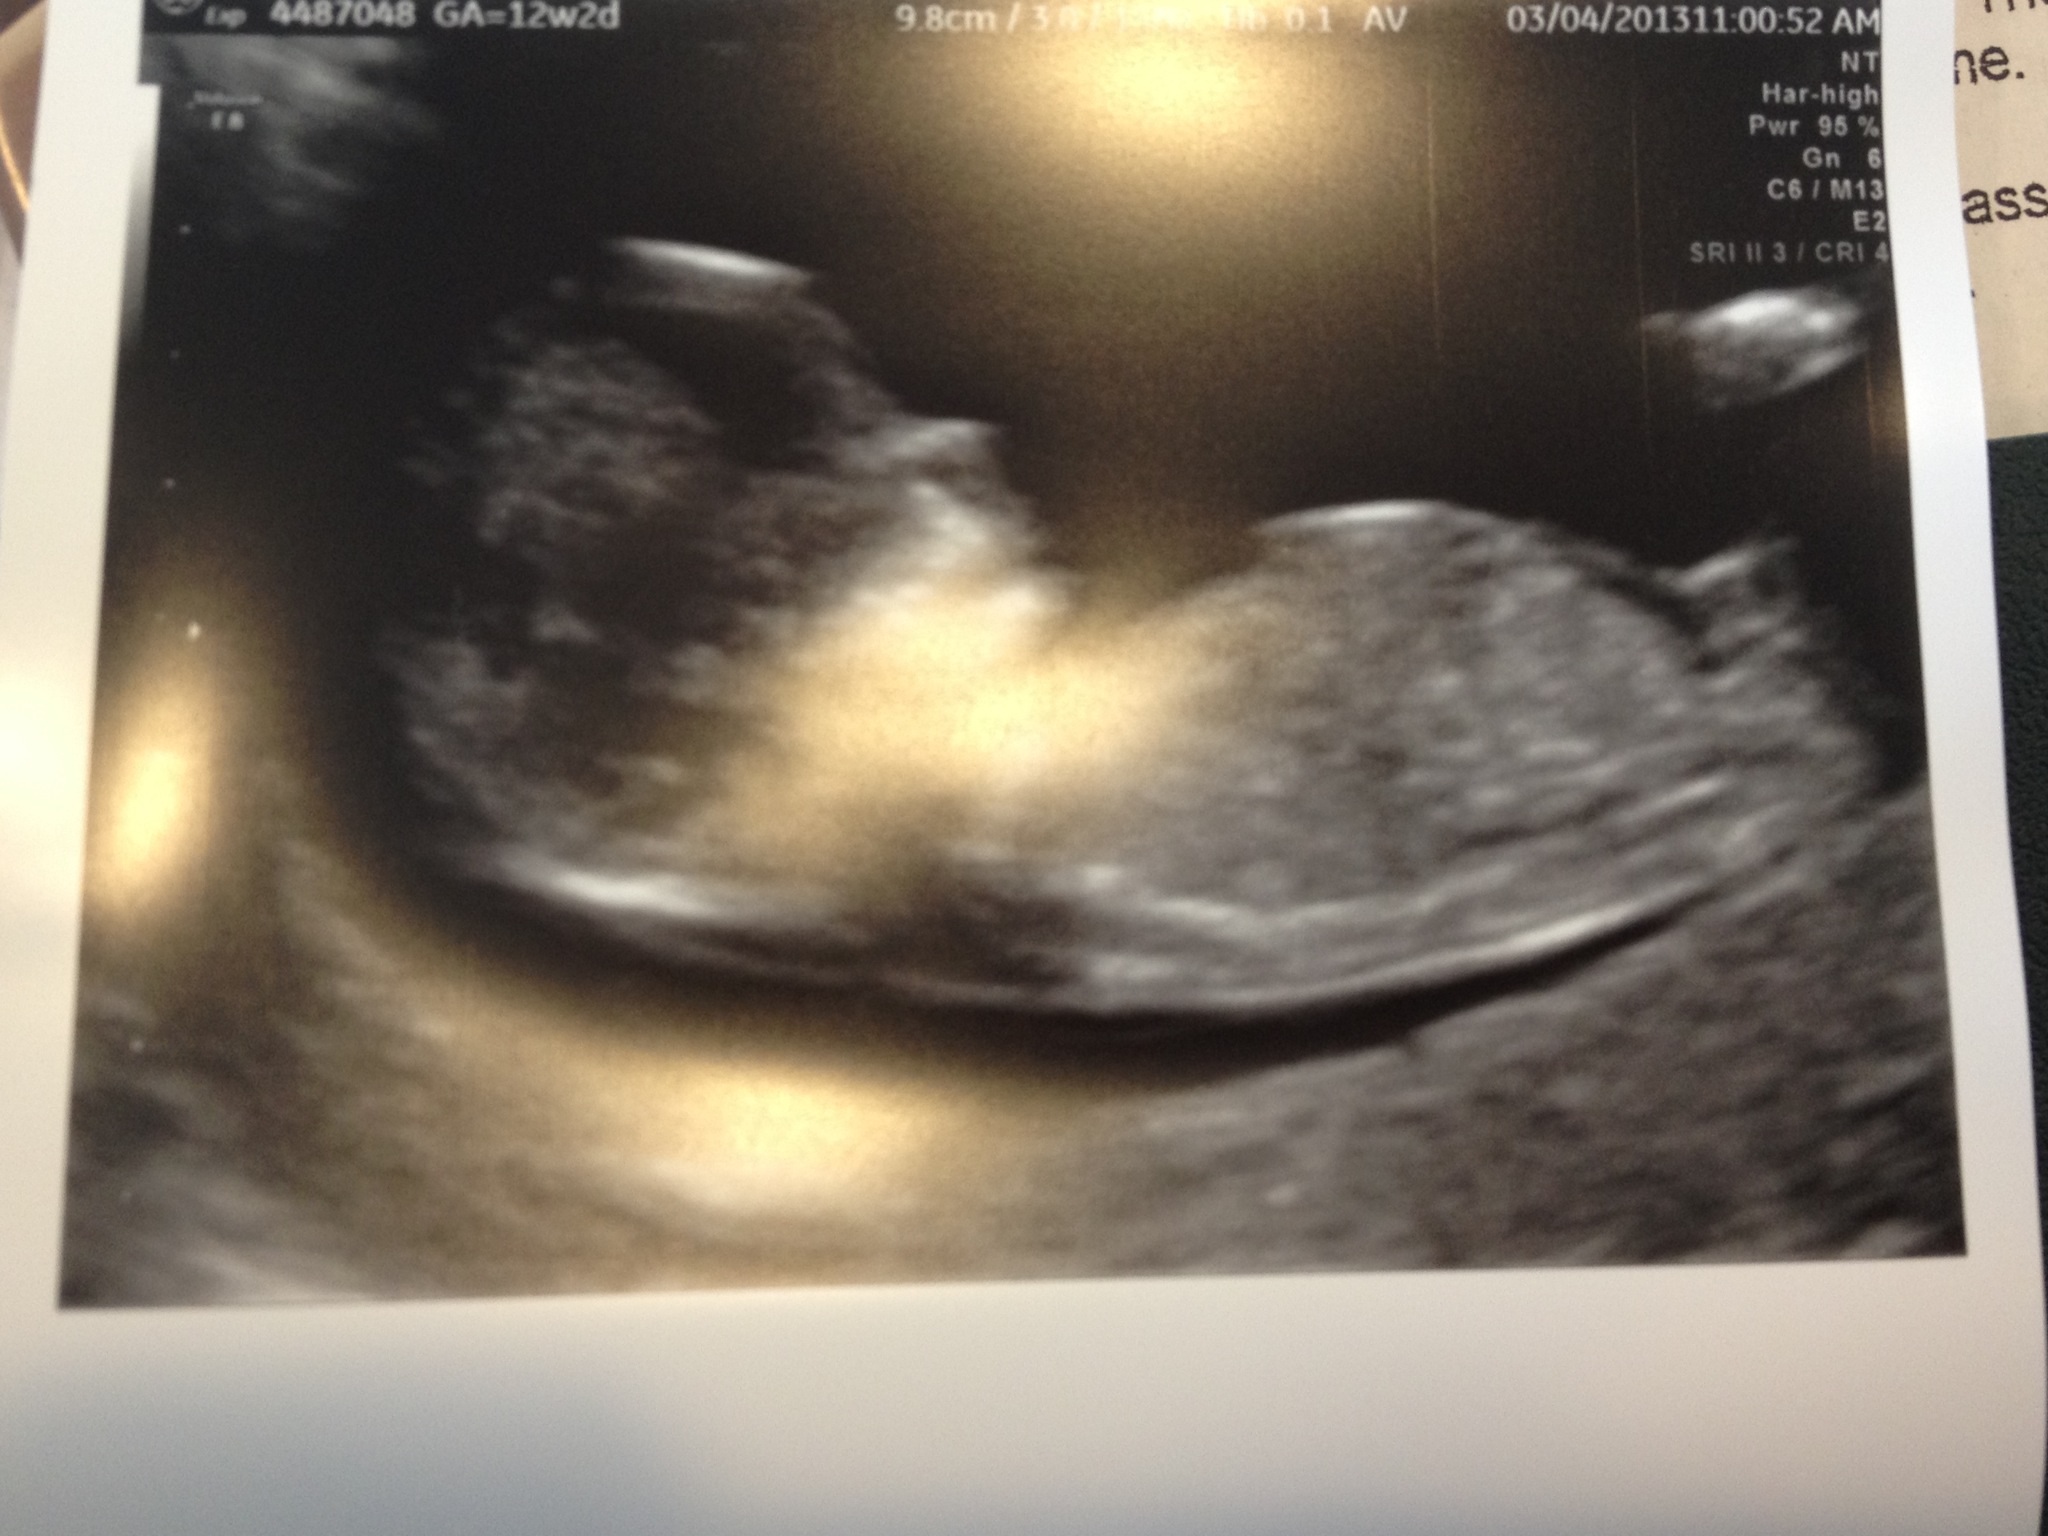

Had my nt Scan today at 12 weeks 1 day. Can anyone see a nub in this pick and take a guess please? I have a few more if this one is not good enough. I think boy but that's just a feeling I have and will love either gender.

Attachment 9383

Can someone tell me if there isn't a nub here and I will post a few other pics.

I can't see a nub clear enough to be sure but I'm thinking girl. The skull to me looks quite girly but I'm no expert on skull and nub guessing.